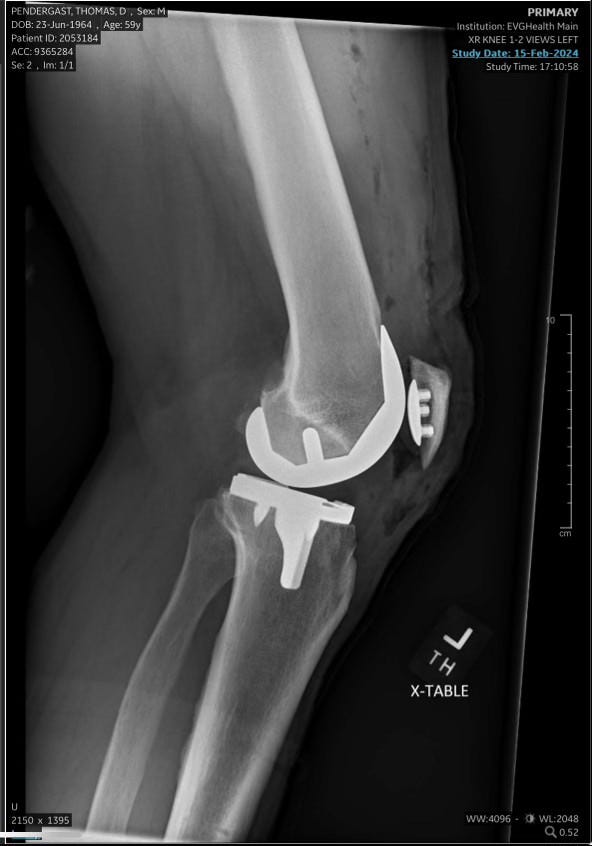

Lest you think I’m kidding about the new joints, consider the following. Now all I have to do is teach them to act like my old joints.